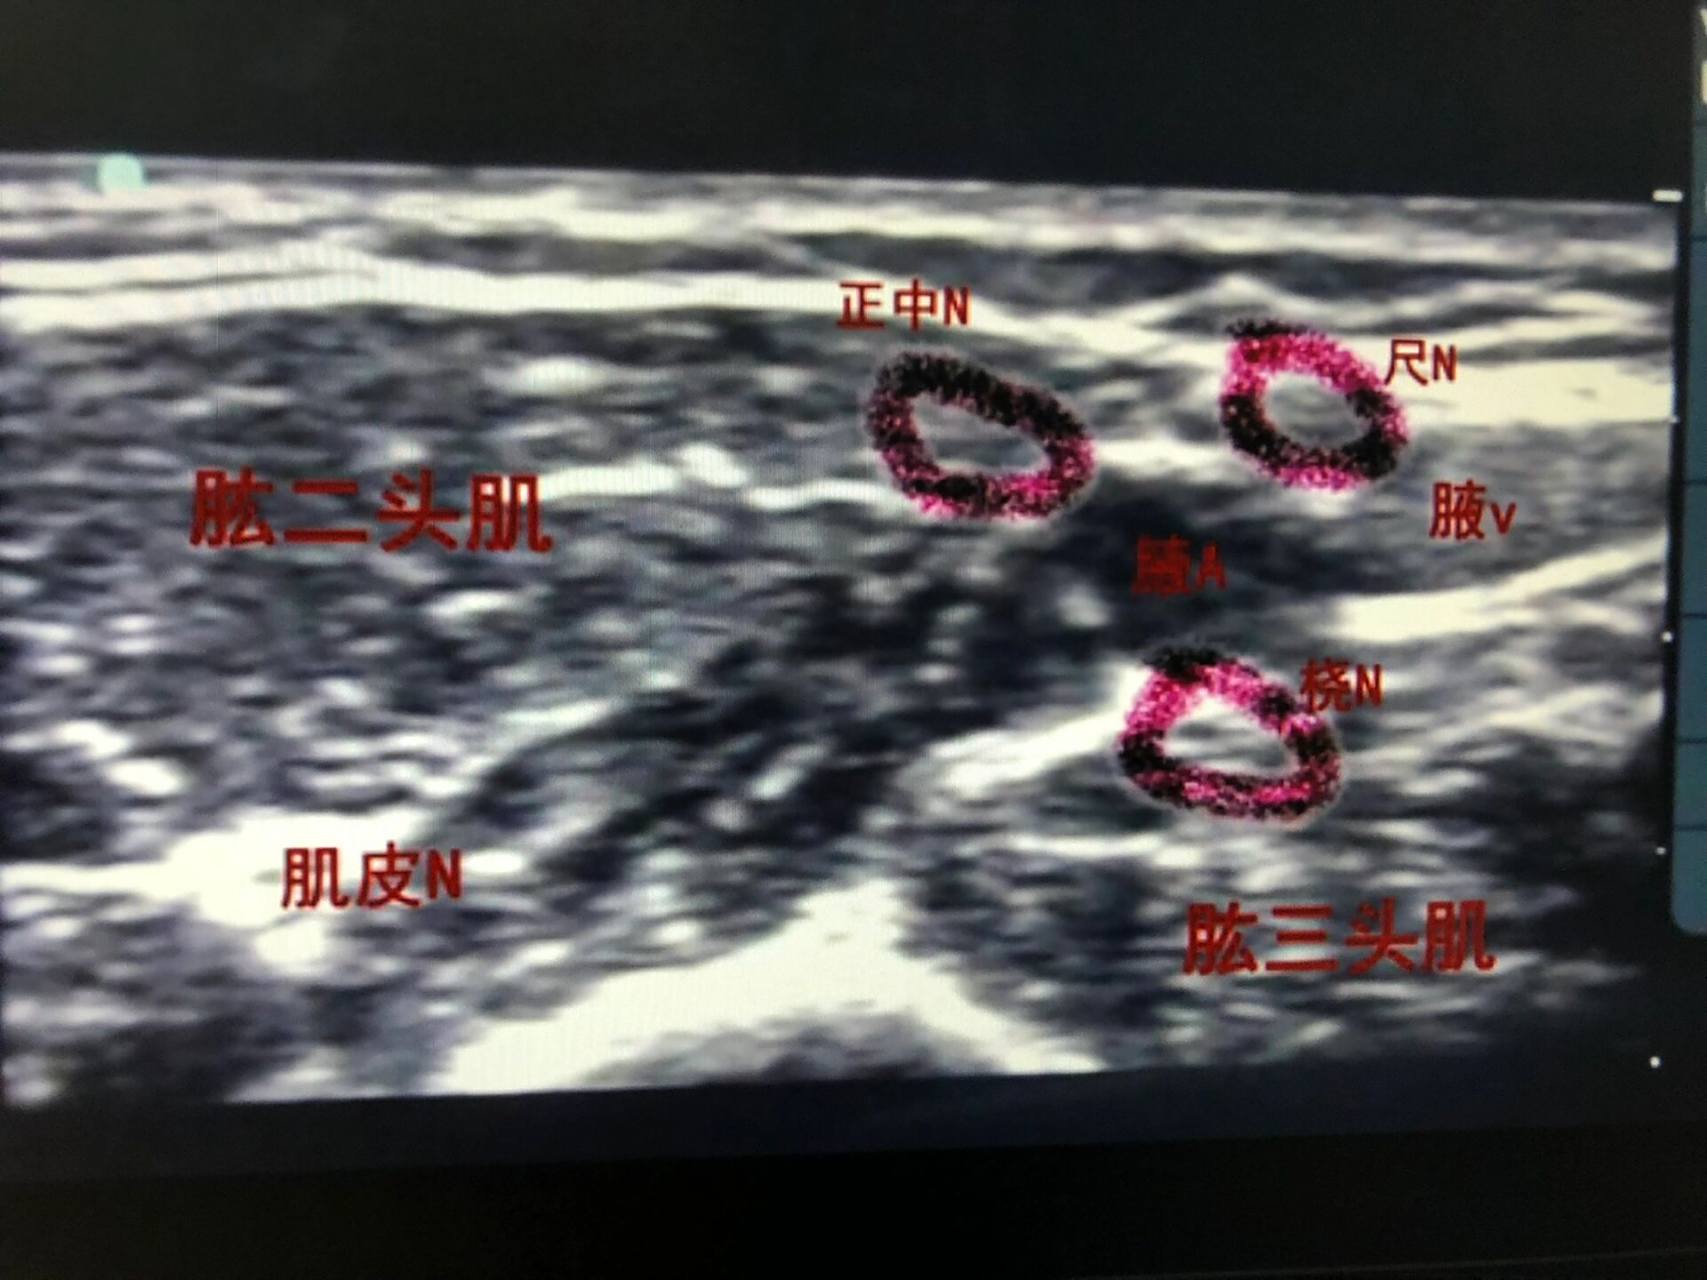

b超下臂丛麻腋路神经分布图 手外伤常做的b超引导下臂丛神经阻滞